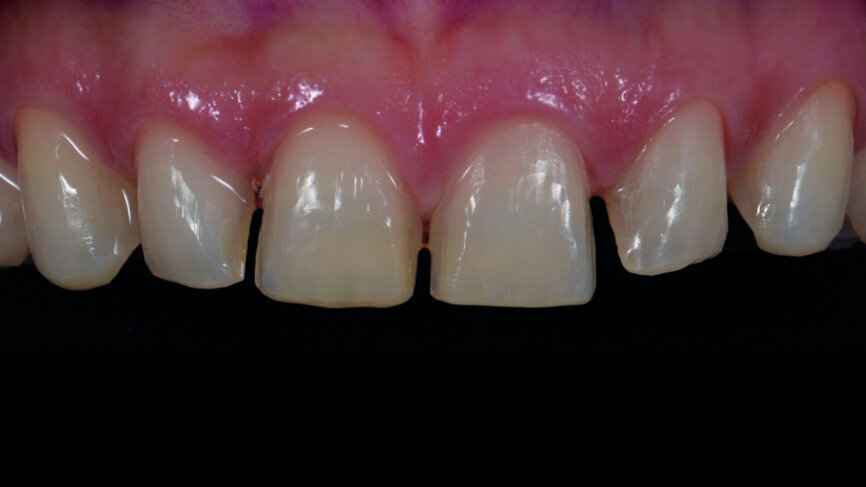

Fig. 2a: Anterior teeth after orthodontic treatment.

A 35-year-old patient presented at the office with the chief desire that the aesthetics in the anterior region be changed (Fig. 1). A diagnostic wax-up was performed, followed by mock-up fabrication, in order to obtain a preliminary visualisation of the final outcome. Orthodontic treatment was proposed in order to align the teeth in a more favourable position for veneers requiring minimal preparation and to reduce the overbite. One year after treatment, the patient returned for the final prosthetic rehabilitation (Figs. 2a & b).